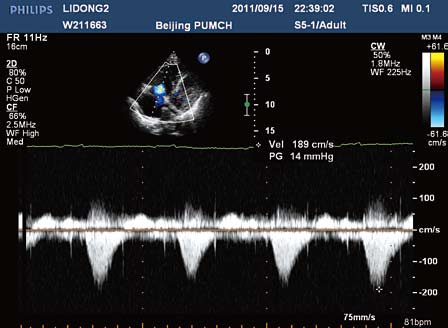

病例解读 心血管 正文内容 经胸超声心动图:左心房,左心室内径增大

术后6月复查超声心动图示左房(38mm)及左室(57mm)较前缩小,二尖瓣